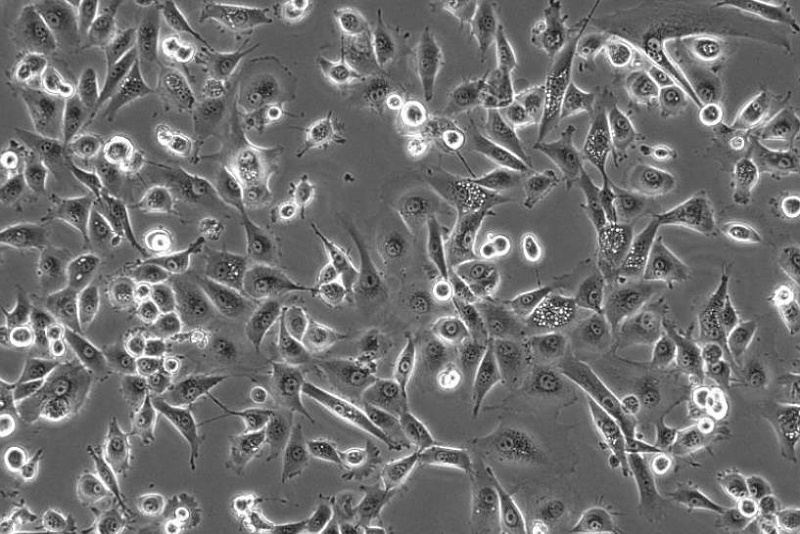

NK細(xì)胞

NK細(xì)胞的目標(biāo)是識別和摧毀異常細(xì)胞,如病毒感染細(xì)胞和癌細(xì)胞。對于健康細(xì)胞來說,它們有一些特殊的機(jī)制,能夠表達(dá)低水平的激活配體和大量的抑制配體,從而不會受到NK細(xì)胞的攻擊。然而,腫瘤細(xì)胞卻常常表達(dá)大量的激活配體和缺乏MHC分子的表達(dá)。NK細(xì)胞能夠感知并響應(yīng)健康細(xì)胞表面表達(dá)的分子庫的變化,定位為對抗癌癥的重要哨兵和癌癥免疫研究的主要目標(biāo)。

隨著對NK細(xì)胞的深入研究,我們對其激活和抑制機(jī)制的理解越來越深入。這為癌癥研究帶來了新的希望??茖W(xué)家們正在努力利用NK細(xì)胞的特殊功能,開發(fā)新的免疫療法來研究癌癥。通過激活NK細(xì)胞或增強(qiáng)其攻擊癌細(xì)胞的能力,可以改善研究效果,并為患者帶來更大的生存優(yōu)勢。

NK細(xì)胞作為免疫系統(tǒng)的重要成員,通過受體信號的調(diào)節(jié)實(shí)現(xiàn)對“正常”和“危險”細(xì)胞的區(qū)分,并發(fā)揮著重要的免疫哨兵作用。對于癌癥研究來說,NK細(xì)胞的發(fā)現(xiàn)和研究為我們提供了新的思路和策略,為研發(fā)更有效的癌癥研究方法帶來了希望。隨著科學(xué)的不斷進(jìn)步,我們相信NK細(xì)胞將在未來的癌癥免疫研究中發(fā)揮越來越重要的作用。